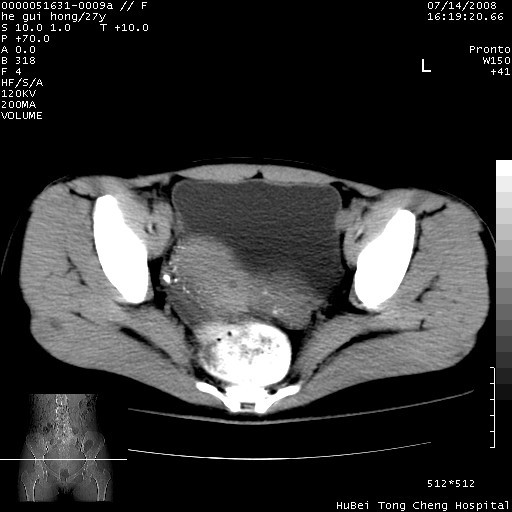

以下是引用杀毒软件在2008-7-20 8:03:00的发言:[br]支持双侧卵巢囊腺瘤可能性大!

以下是引用zjzjr在2008-7-20 13:36:00的发言:[br]双侧附件囊腺瘤可能性大!